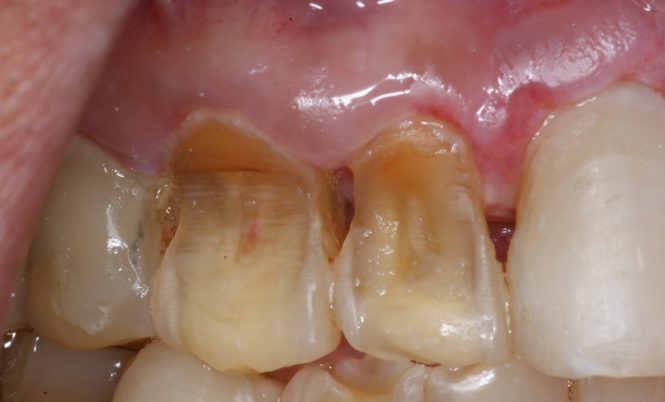

Translucency on the incisal edge of a tooth and intact gingival margin may indicate moderate erosion. In severe cases, the morphology of the tooth becomes significantly altered, which may lead to dentin and/or pulp exposure (Figure 4). The white translucent enamel becomes worn from the surface, leaving yellow dentin and reddish pulp. Worn incisal edges of teeth can be prone to further weakening and fractures. Exposed dentin can cause hypersensitivity to cold, hot, and tactile stimuli.21 If untreated, an exposed pulp may be susceptible to infection and necrosis.

Fig 4. Facial erosion with aggressive abrasion of maxillary anterior teeth. Note pulp exposure on facial surface of canine.

Figure 4